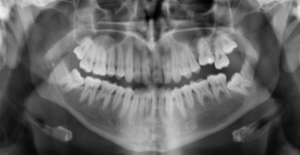

Figure 5: X-ray showing mixed primary and permanent teeth of an eight-year-old boy

Figure 6: X-ray showing permanent dentition[20]

Radiographic appearance

On radiographs, enamel appears as the most radiopaque (white) structure due to its high mineral content.[19] Dentine and cementum are less radiopaque and are usually indistinguishable from each other.[19] The pulp chamber and root canals are radiolucent (dark), centrally located within the tooth structure. The periodontal ligament appears as a thin, radiolucent line between the root and the lamina dura.[19]